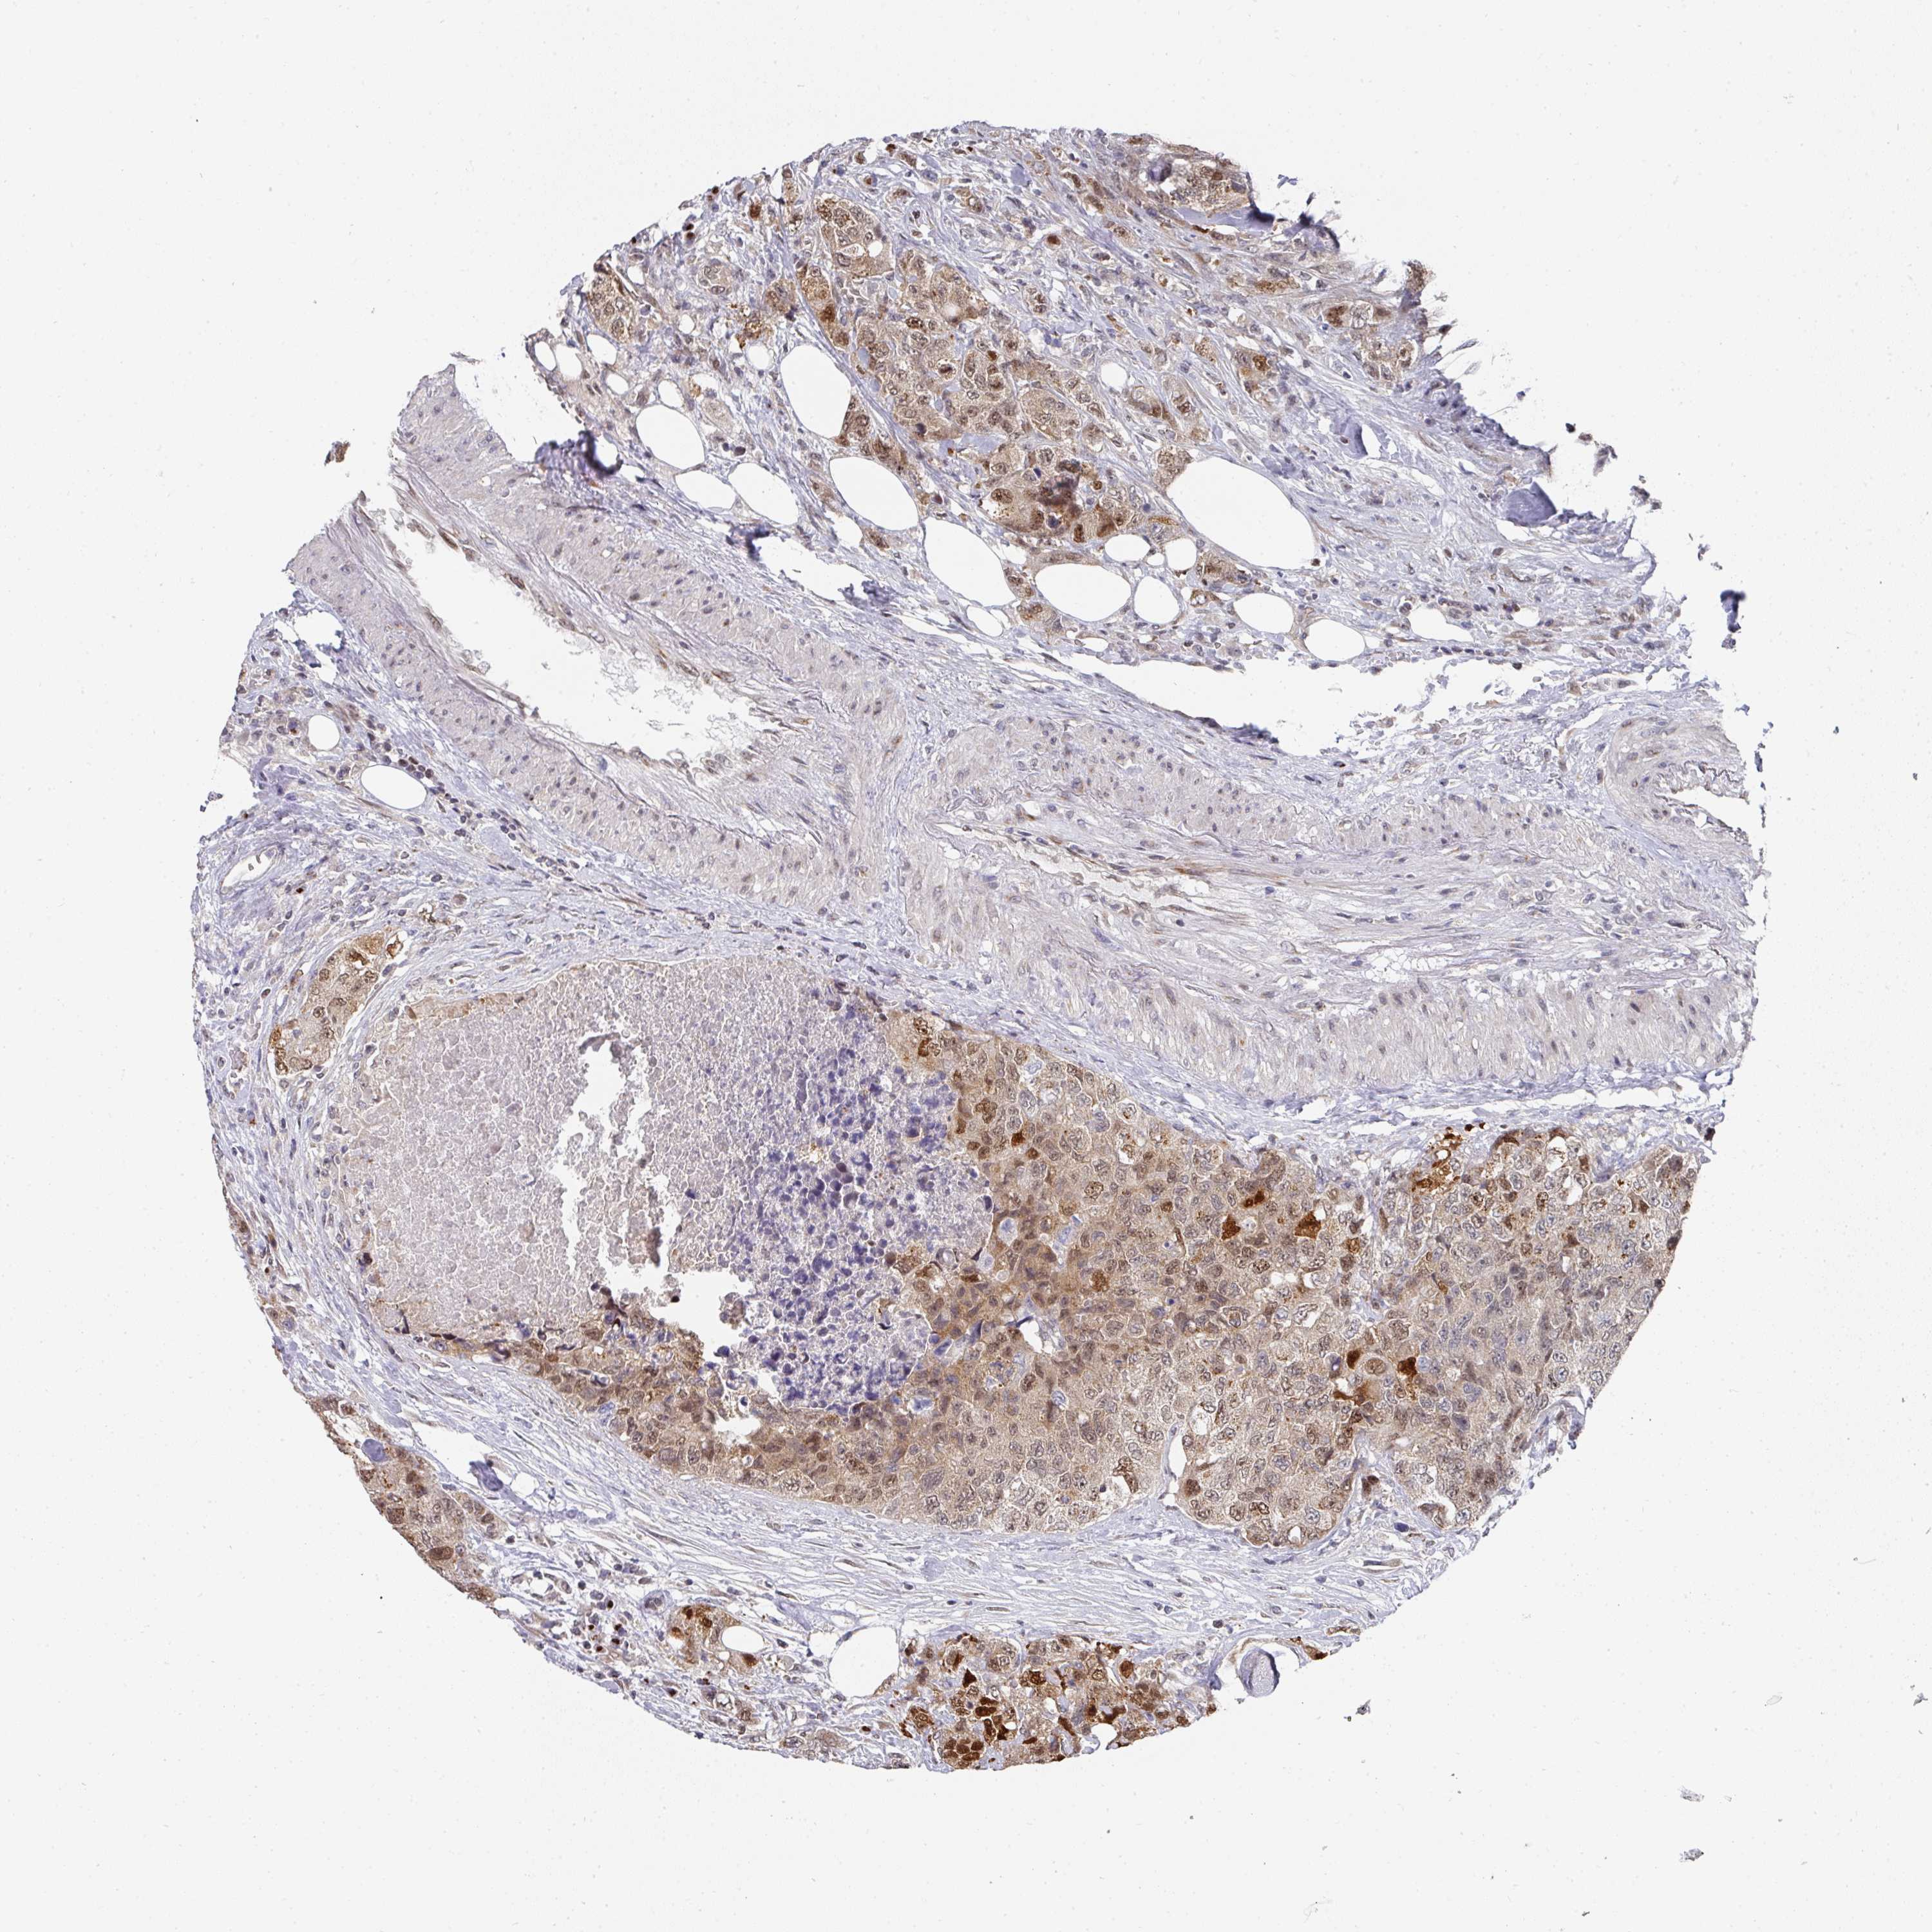

UROTHELIAL CANCER - Protein expressioni

A mouse-over function shows sample information and annotation data. Click on an image to view it in a full screen mode. Samples can be filtered based on level of antibody staining by selecting one or several of the following categories: high, medium, low and not detected. The assay and annotation is described here.

Note that samples used for immunohistochemistry by the Human Protein Atlas do not correspond to samples in the TCGA dataset.

Antibody stainingi

Antibody staining in the annotated cell types in the current human tissue is reported as not detected, low, medium, or high, based on conventional immunohistochemistry profiling in selected tissues. This score is based on the combination of the staining intensity and fraction of stained cells.

Each image is clickable and will lead to virtual microscopy that enables deeper exploration of all samples and also displays staining intensity scores, fraction scores and subcellular localization as well as patient and tissue information for each sample.

Antibody HPA051314

Staining

High

Medium

Low

Not detected

Intensity

Strong

Moderate

Weak

Negative

Quantity

>75%

75%-25%

<25%

None

Location

Nuclear

Cytoplasmic/membranous

Cytoplasmic/membranous,nuclear

Urothelial carcinoma, High grade

Urothelial carcinoma, NOS

Urothelial carcinoma, Low grade